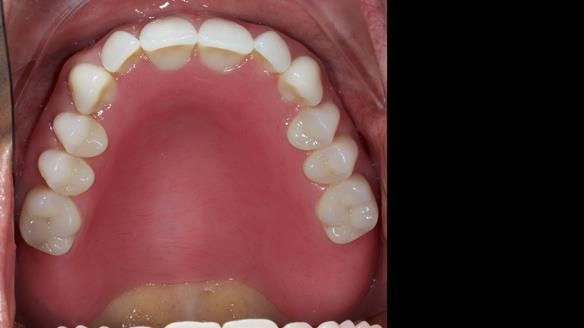

She had previously suffered from generalised periodontitis – stage IV, grade C, currently stable, with reduced attachment across the upper arch.

By the time she came to me, her periodontal condition was stable — but the aesthetics in the upper jaw were very poor.

We provided her with an immediate upper denture (Mk 1), followed by a definitive metal-based upper denture (Mk 2). A lower removable partial denture was discussed, to be made only if needed once the upper treatment was complete. However, at review, this wasn’t necessary — Adnana had excellent neuromuscular control and function, even with a shortened dental arch (SDA).

- Definitive denture (Mk 2), metal-based and custom-designed for her face